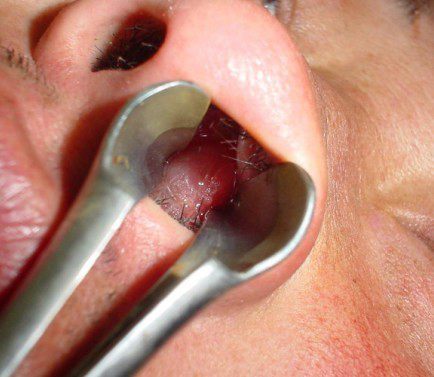

鼻腔巨大息肉

以鼻塞,头痛,浓涕为主要症状,特别是那些较大的鼻息肉,长期的存在会